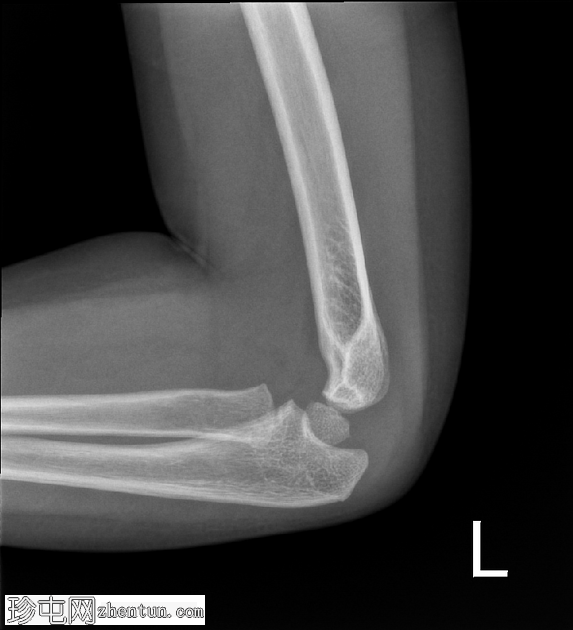

4.png

斜位

在正位片和侧位片上,桡骨近端干骺端可见轻微的皮质断裂和不规则,骨折线似乎向骺端延伸。

相关的脂肪垫征(可见前脂肪垫和帆状征,后脂肪垫阳性)进一步支持骨折后关节内积液的存在。

总体而言,骨性对线保持良好,无脱位迹象。

骨化中心与年龄相符。